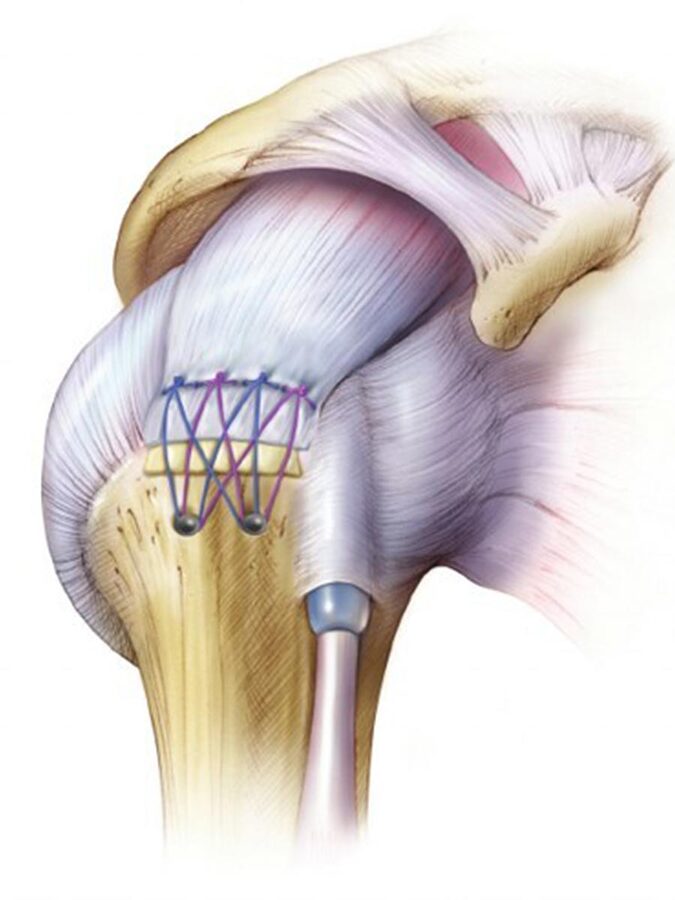

¿En que consiste la intervención? Mediante la artroscopia y la colocación de anclajes se reparan los ligamentos, así como el labrum.